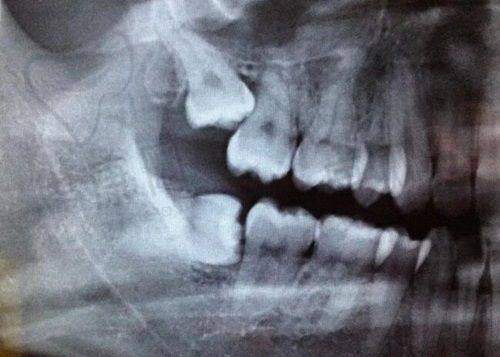

云南昆明竹子口腔医院是卫生计委批准设立的口腔专科门诊部,也是五华区政府特别招商引资项目,具有正规的医疗资质。医院位于昆明市中 心金马碧鸡坊招银大厦1 - 3层,占地面积达2200平米,拥有宽敞舒适的就诊环境。作为口腔专科连锁机构,自2018年落户云南昆明以来,积累了丰富的临床经验和良好的口碑。同时,它还是医疗保险定点单位,以人人都可承受的消费水平,为昆明市民带来实惠的看牙体验。在儿童早期矫正方面,医院配备了精良的医疗设备,能够正确地对儿童牙齿进行检测和分析,为制定个性化的矫正方案提供有力支持。